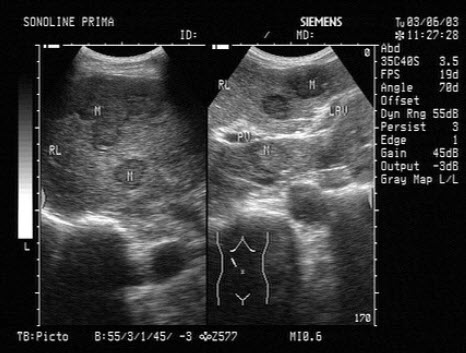

5、单项选择题

某患者脾脏声像图表现如图,诊断为()

A.正常脾脏

B.脾大

C.脾破裂

D.脾梗死

E.以上都不是